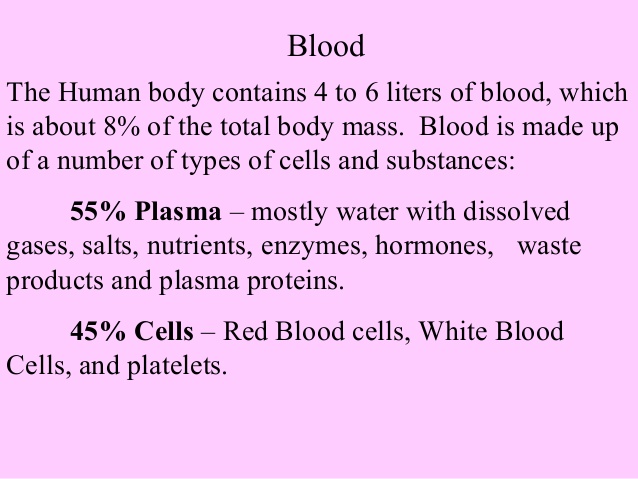

- Components of blood and their functions (Red blood cell, white blood cell, platelets and plasma (blood groups)